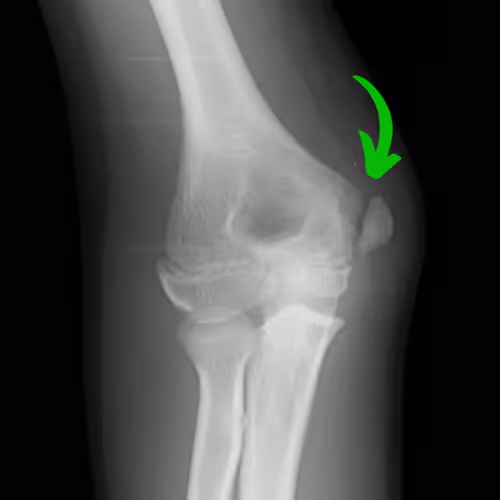

Diagnosis of little league elbow is typically done via clinical examination with a history of throwing and pain on the inside of the elbow. Diagnosis is confirmed via x-ray that shows a small separation of the growth plate on the medial epicondyle.

The most common complication of little league elbow is an avulsion fracture of the medial epicondyle. This is a relatively rare, but significant complication that happens in roughly 16% of little league elbow cases. This is most commonly found in athletes who continued throwing through pain or ignored medical guidance for a period of rest to recover from little league elbow.

Management of an avulsion fracture can vary based on the amount of displacement between the fracture and the bone. Some athletes may require a surgical fixation to ensure adequate healing.